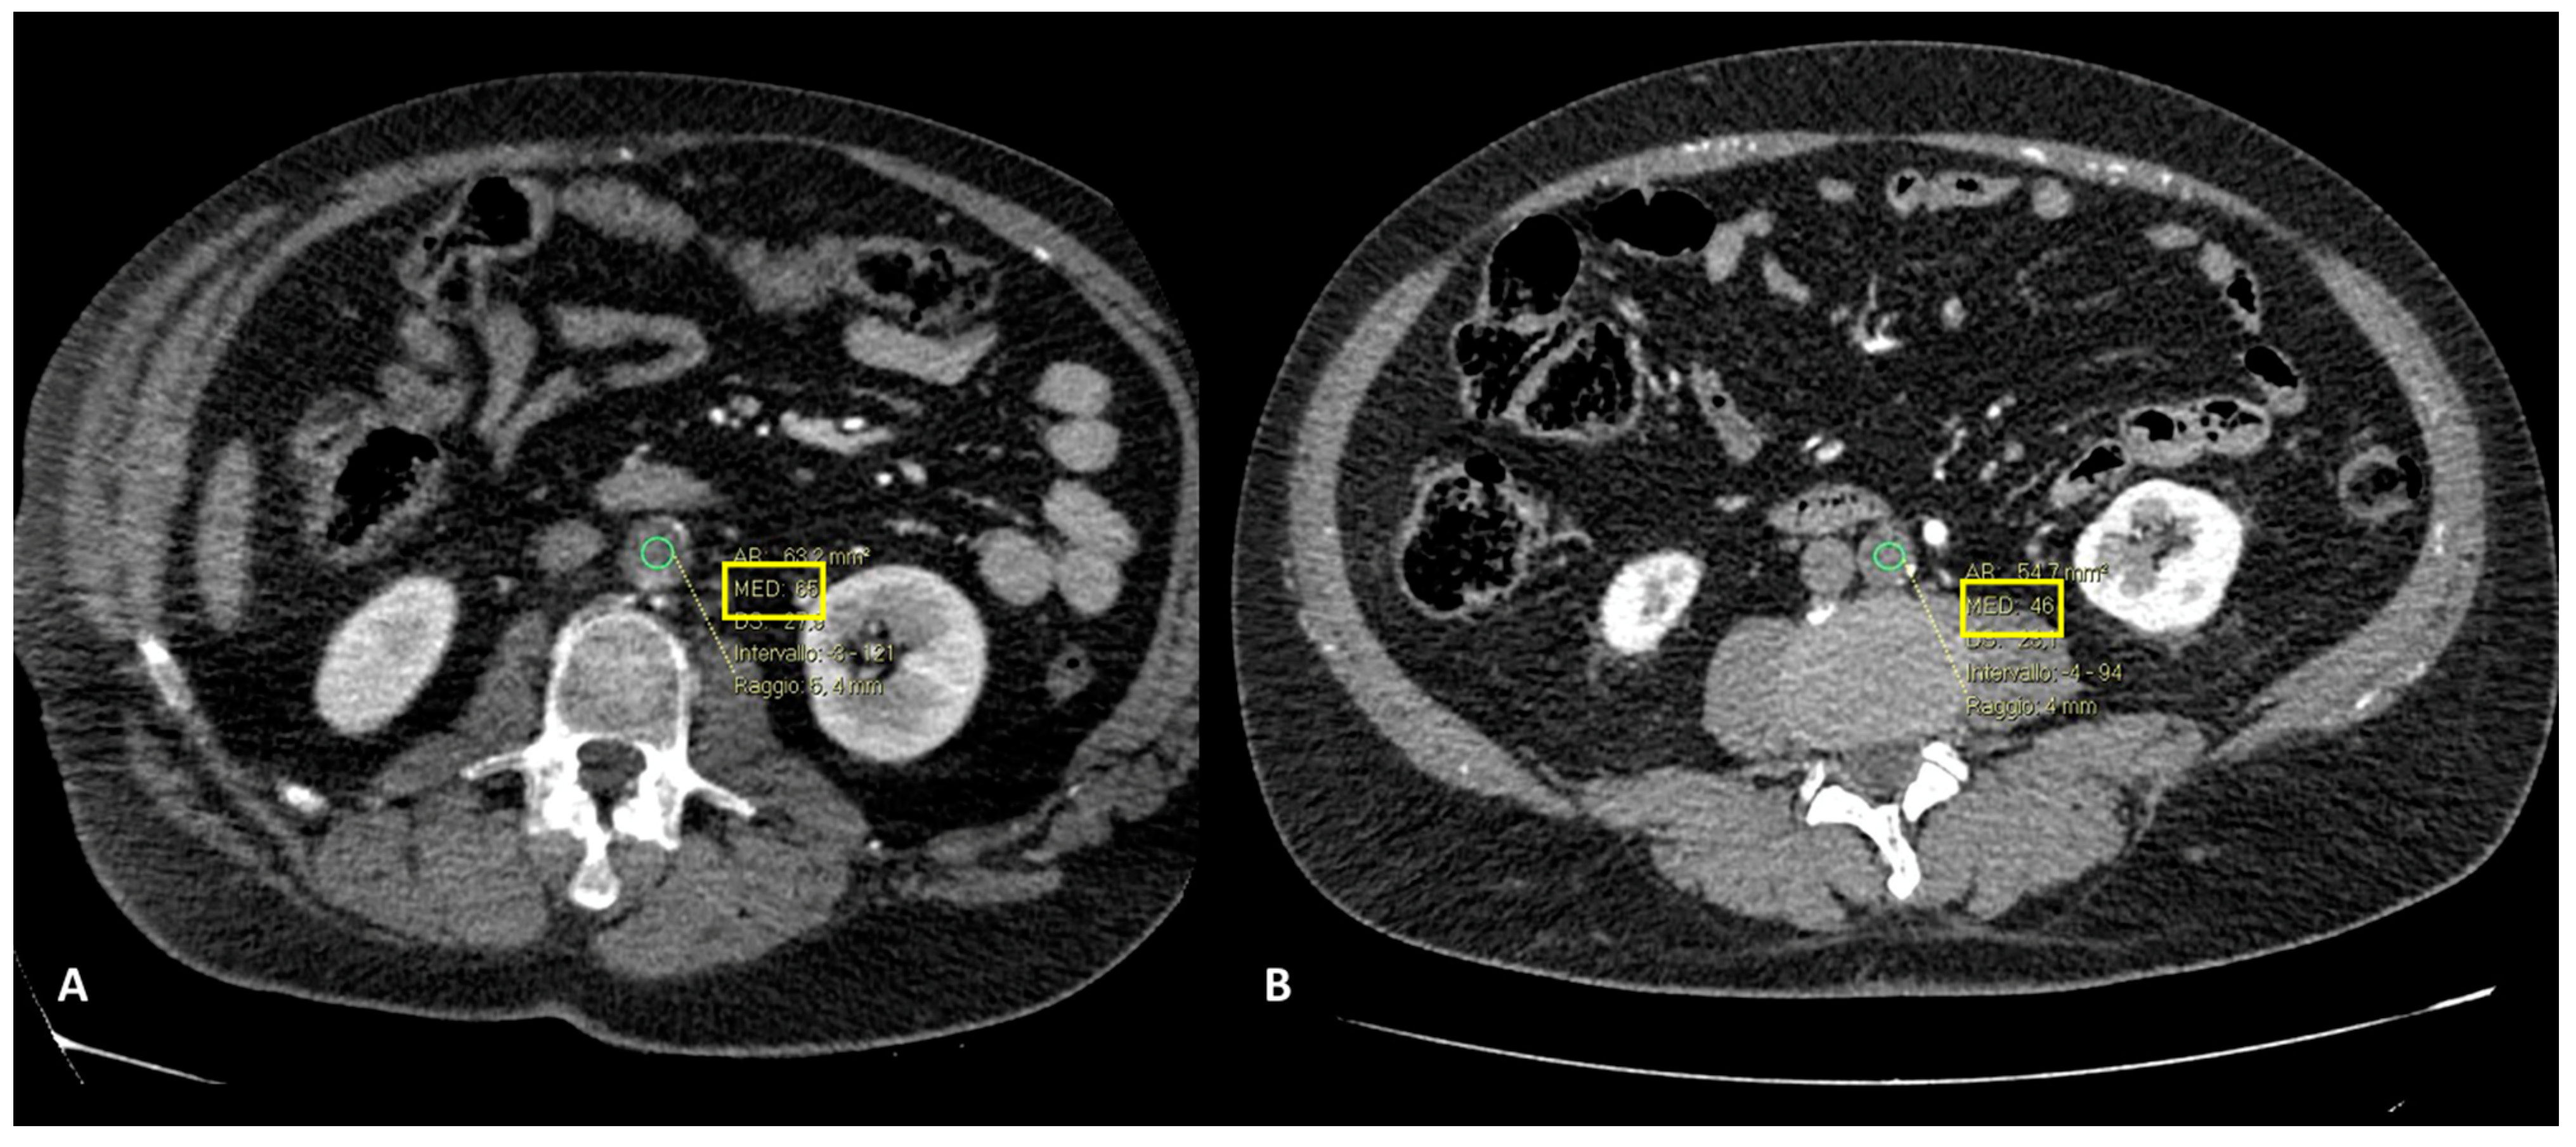

- In one case (9.1%), hypoperfusion of the intestinal loops was evidenced due to extensive thrombosis of the superior mesenteric artery (Figure 5); this patient was the one with predominant abdominal pain symptoms.